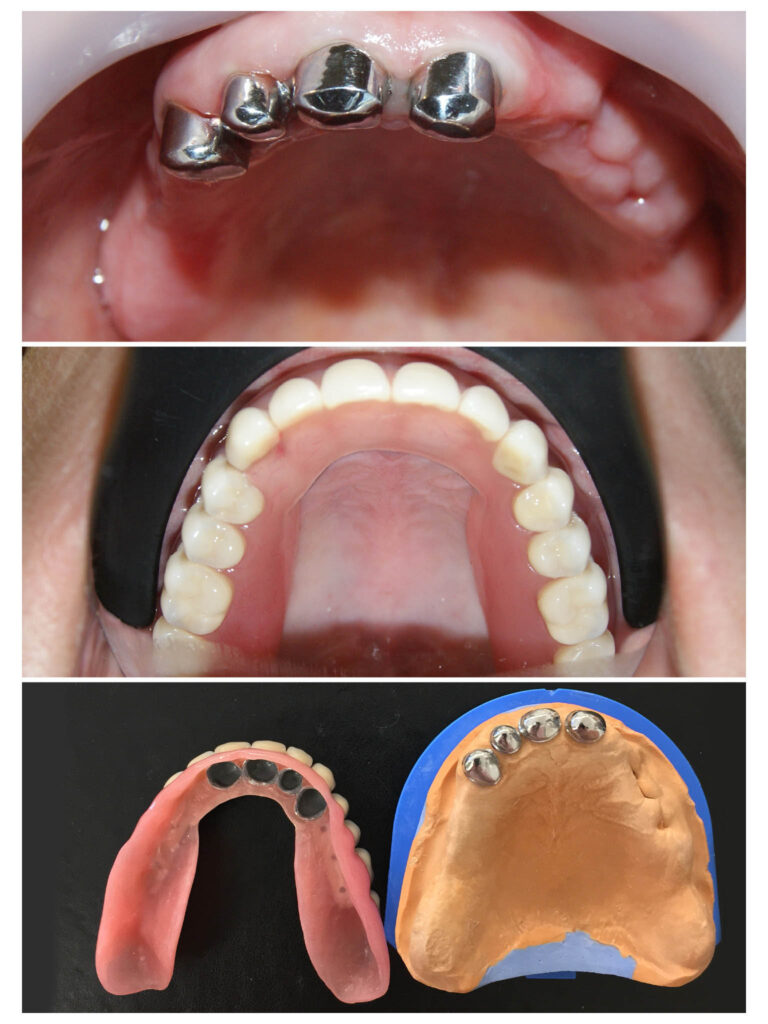

Lucrare fixată pe dinți împreună cu proteză scheletată mobilizabilă = soluția de lux pentru dinți puțini